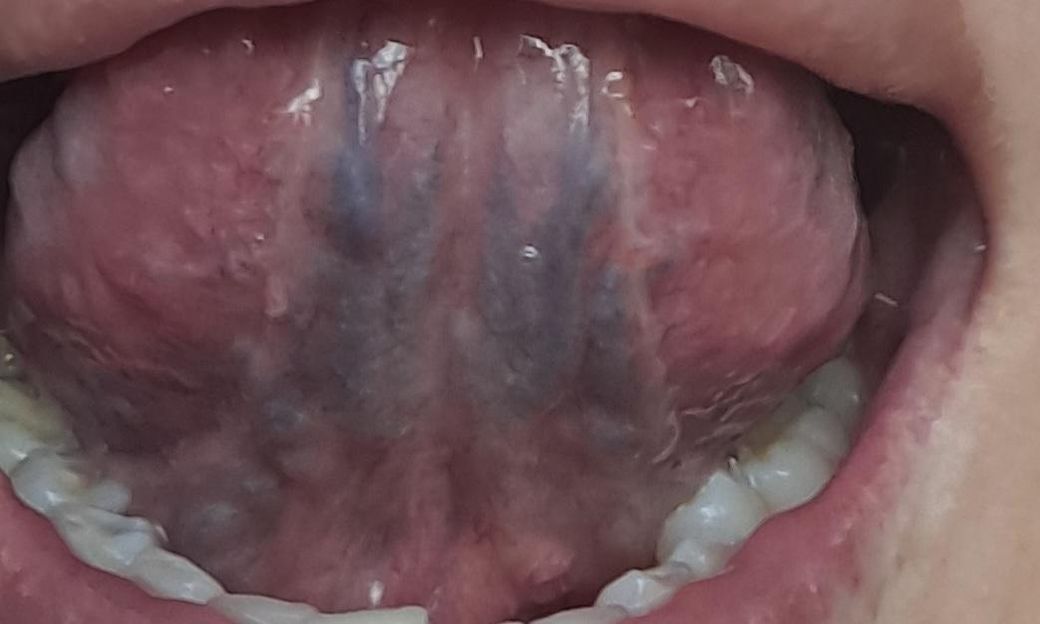

구강유두종 증상인지 궁금합니다. 병원은 어디로

최근 콘딜로마 치료중인데 혹시 구강에도 올라온것이 콘딜로마인지 정상조직인지 궁금합니다ㅜ 병원은 어디로 가야할까요? 치과인지 이비인후과인지...

• 2번 째 사진

특이소견으로 생각되지 않으나, 보다 적절한 평가 시행 위해 이비인후과 내원하여 진료 봐보실것 권유드립니다. 답변 도움되었기 바랍니다. 감사합니다.

콘딜로마의 가능성이 높아 보이지는 않습니다만, 진료를 받아보셔서 정확한 진단을 받아보시기를 바랍니다.

갯수가 늘어나거나 크기가 커지는 것이 아니라면, 임상적으로 콘딜로마의 가능성은 떨어집니다.